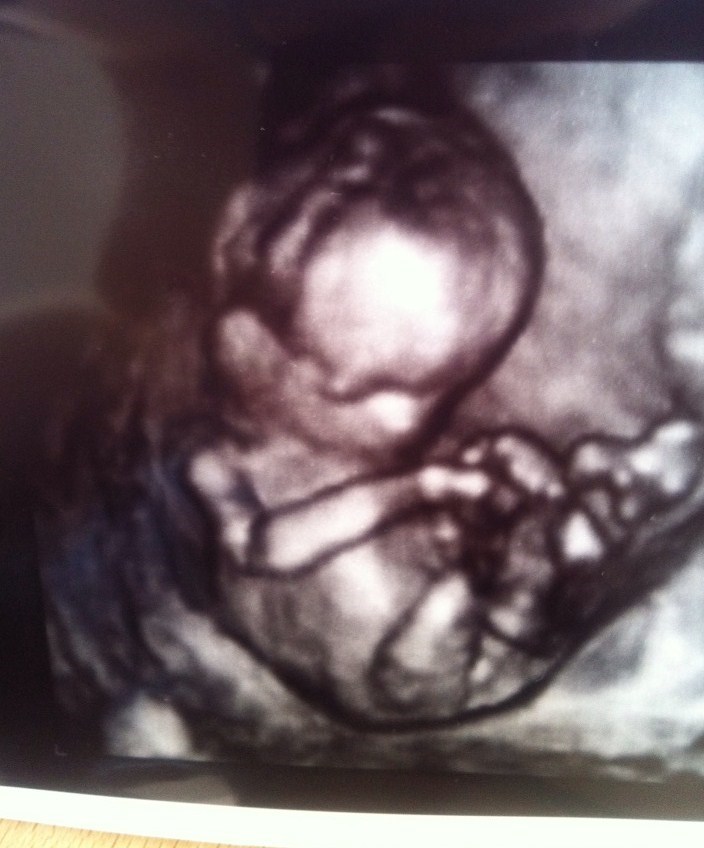

Hej alle kommende december mødre. Vi har i dag været til kønsscanning, og vi venter en sund og raske lille pige! Hooold nu op, hvor er hun smuk! .

Vedhæftede fotos (klik for at se i fuld størrelse)

tillykke hvor skønt, hvilke en af kønsscaningerne valgte du? den til 500kr i 2D eller den til 700kr i 3D. Vi skal derind d.15

Vi tog den til 700, den er mere værd, synes vi!